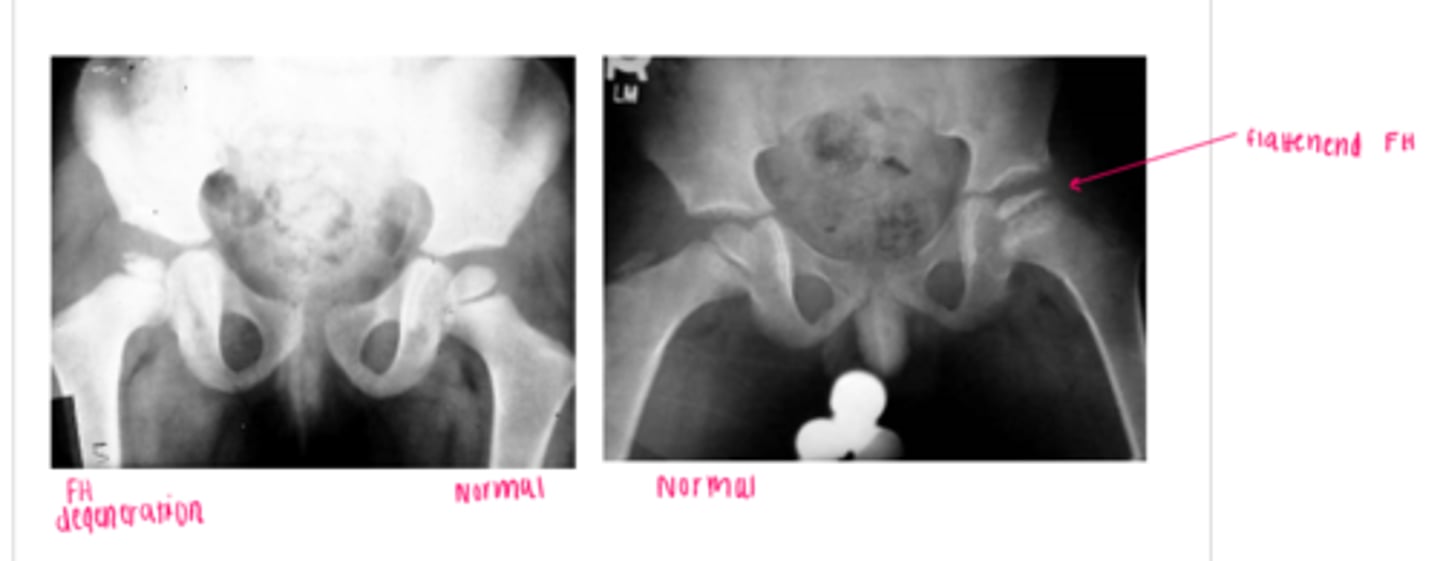

Legg-Calve-Perthes Disease

a type of osteochondrosis or disease of the growth centers in children which begins as a degeneration followed by regeneration and recalcification

*unknown etiology

**more likely in males, onset is generally 5-7 yrs of age (3-13)

FUNCTIONAL DEFICITS--> pain, limited ROM, gait changes

COMPENSATORY MOVEMENTS--> limit motion/use of the joint, limit overall activity level

COURSE--> bone necrosis, revascularization, reossification over a period of 24-36 months